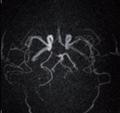

GHUPPN will evaluate specific MR sequences for brain tumor and acquire a better understanding of the evolution of brain gliomas by deeply analyzing their spatial organization and get a better delineation between tumors and surrounding benign brain parenchyma. A second research priority is to develop and evaluate contribution of contrast-free MR angiography for head and neck vessels and compare to current gold-standard MR angiography with contrast-media injection. Leveraging its extensive expertise in Psychiatry, GHUPPN is also planning to use the Vantage Galan 3T/ Saturn X Gradient to evaluate the contribution of dedicated MR pulse sequences for children and teenagers with psychiatric disorders and cognitive development limitation.

Atlas SPEEDER Head/Neck, T2, AiCE, Res: 0.2 x 0.2 x 2 mm, Scan time: 6:35 min.

Brain – Hippocampus